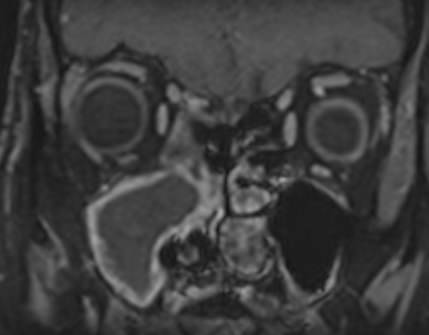

Чаще всего пазухи носа подвержены воспалительным процессам. В зависимости от поражения той или иной пазухи различают гайморит, фронтит, этмоидит, сфеноидит. Реже встречаются доброкачественные и злокачественные опухоли придаточных пазух носа.

МРТ является высокоинформативным способом визуализации данных анатомических областей. Метод позволяет диагностировать различные патологические процессы в области придаточных пазух носа. Кроме высокой информативности МРТ обладает такими преимуществами как достаточная быстрота, безболезненность и безопасность. Метод основан на использовании действия на ткани внешнего магнитного поля, при этом не применяется вредное рентгеновское излучение.

В случае подозрения на развитие опухолевого процесса в обязательном порядке показано введение контрастного вещества для лучшей визуализации патологических изменений в тканях. Степень и характер накопления контрастного препарата в органах и тканях позволяет различать патологические процессы, в том числе диагностировать опухоли на ранних стадиях. Так контрастирование помогает выявлять новообразования размером от 1 мм, что повышает шансы пациента на получение своевременного лечения и выздоровление.